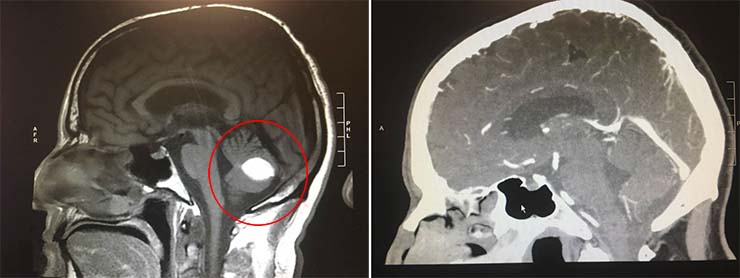

Wood por su parte, está seguro que la curación fue posible gracias a su fe y a las oraciones que muchas personas hicieron a su favor. “Si no crees en Dios y crees que no hace milagros, explica esto. El tumor desapareció y los médicos no puede explicarlo, están de acuerdo en que se trata de un milagro”, escribió Paul en su cuenta de Facebook, donde muestra una tomografía de su cabeza que le hicieron en el hospital.

“En la tomografía, en la parte inferior derecha se puede ver el tumor en el lugar del círculo blanco, ahora ha desaparecido”, comentó Wood. Los médicos que atendieron a este paciente han quedado tan intrigados con su inexplicable recuperación, que han decidido pedirle que se ofrezca como voluntario para participar en unas investigaciones.